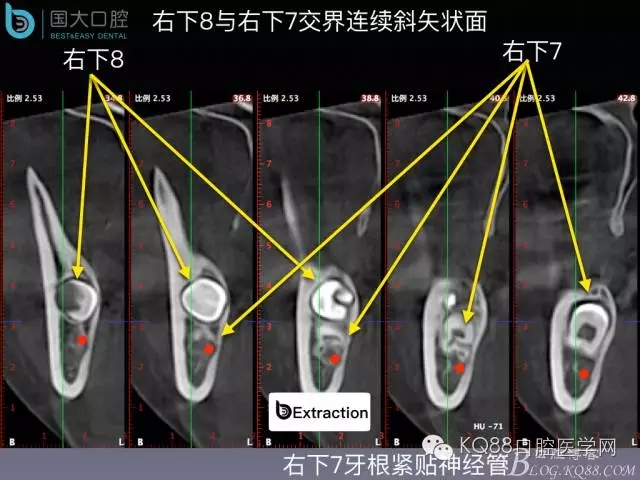

阻生牙的預(yù)防性拔除